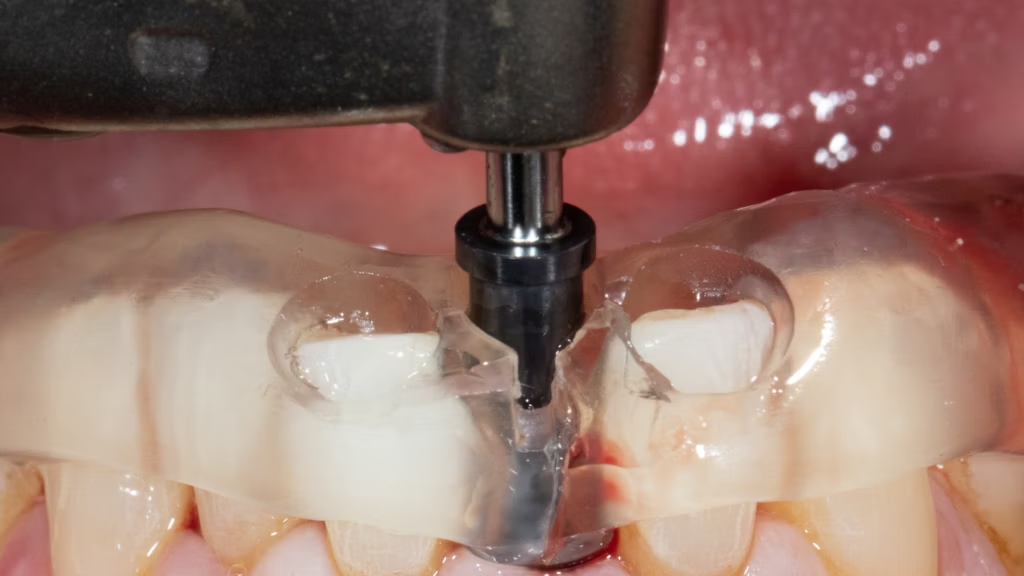

Digitally Guided Implant Surgery and Restoration for Single Tooth Replacement

Step into the future of dental implantology with this cutting-edge course on digitally guided implant surgery and restoration. Led by Dr. Edwin Wijaya, this session covers advanced techniques for precise single tooth replacement, all in just 60 minutes.